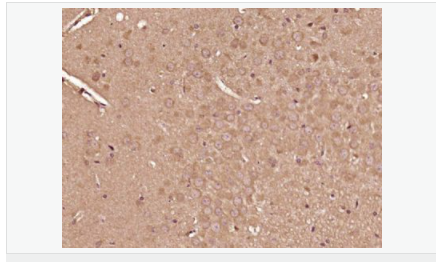

產品介紹This gene encodes the insulin receptor substrate 2, a cytoplasmic signaling molecule that mediates effects of insulin, insulin-like growth factor 1, and other cytokines by acting as a molecular adaptor between diverse receptor tyrosine kinases and downstream effectors. The product of this gene is phosphorylated by the insulin receptor tyrosine kinase upon receptor stimulation, as well as by an interleukin 4 receptor-associated kinase in response to IL4 treatment. [provided by RefSeq, Jul 2008]

IRS-2是肝胰島素信號轉導核心介子,IRS-2基因的缺失或IRS-2信號網絡上一些關鍵信號分子的異常改變,都將導致肝胰島素信號轉導能力減弱,出現肝胰島素抵抗.